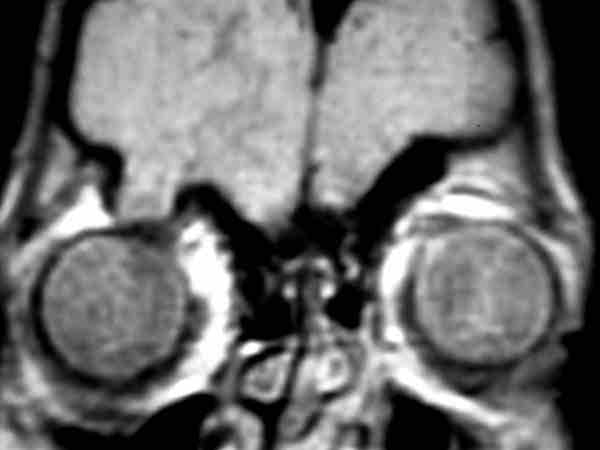

58-09.jpg (12120 bytes)

Figura 9. Acumulos de LCR dentro de las vainas del nervio óptico vistos en una plano axial de RM. Paciente con hipertensión endocraneal benigna.

La técnica de fenestración de las vainas del nervio óptico ha resurgido como método de tratamiento de la hipertensión endocraneal benigna en la última década (30-32). En muchos de los casos se ha convertido en el procedimiento de elección con una eficacia que alcanza el 90%. La mayoría de paciente tratados con esta técnica presentaban hipertensión endocraneal crónica con edema de papila y afectación del nervio óptico. La técnica se ha mostrado eficiente también en otros tipos de hipertensión endocraneal secundarios a hidrocefalia, tumores cerebrales y trombosis de senos venosos intracraneales (33). La mayoría de autores creen que el mecanismo de reducción de la presión intracraneal es el filtrado de LCR hacia la órbita desde las fenestraciones de las vainas de nervio ópticos. El acceso al nervio para realizar estas fenestraciones puede ser hecho por una vía medial o por una vía lateral. En ambos casos se debe abrir bien tanto la duramadre como la aracnoides del nervio óptico permitiendo la salida de LCR hacia la órbita.